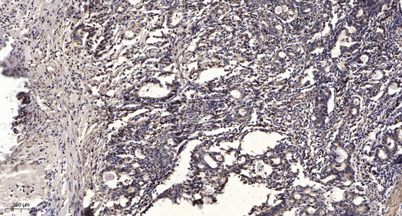

IHC

IHC-p 1:50-300